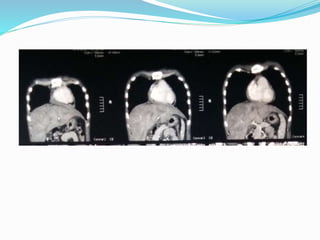

IMAGING

CT Chest Report

 CT/MRI : Thickened pericardium (>4mm) in a patient

with a hemodynamic profile consistent with CP

physiology is considered diagnostic.

 Computed Tomography (HRCT)

 Pericardial thickness

 Degree of calcification

 Distribution of these findings

 Pericardial thickening >4 mm assists in differentiating

constrictive disease from restrictive cardiomyopathy, and

thickening >6 mm adds even more specificity for

constriction.

Normal pericardial thickness does not exclude pericardial

constriction, and the clinical situation must always be taken in

account.